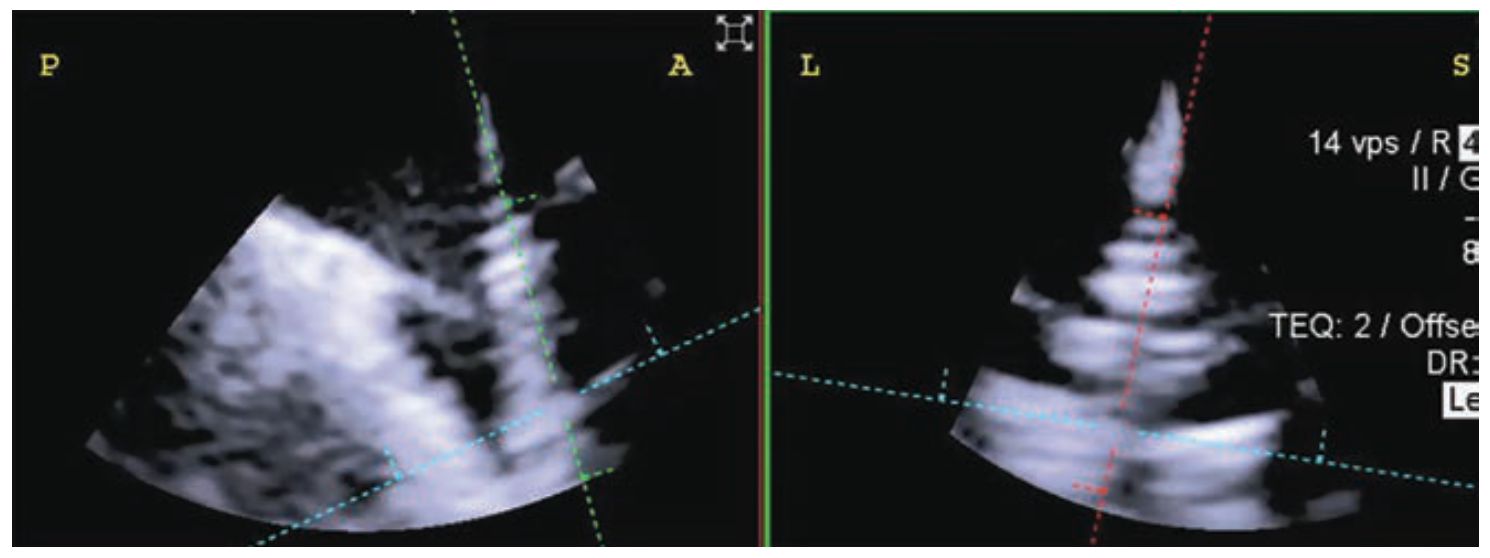

Transesophageal echocardiography (TEE) is considered the gold standard for image guidance during tricuspid valve repair. However, the ability to position the TEE ultrasound probe is limited by the esophageal path, the distance to the tricuspid valve, and challenging transgastric en-face views. Four-dimensional intracardiac echocardiography (4D ICE) overcomes TEE’s limitations and provides unobstructed adjacent views of the tricuspid valve and leaflet anatomy. In this case, a patient with severe tricuspid regurgitation (Figure 1) presented for tricuspid transcatheter edge-to-edge repair (TEER). The use of TEE with an ICE catheter (the ACUSON AcuNav Volume ICE catheter, Siemens Healthineers) provided detailed views of tricuspid leaflet anatomy (Figure 2), enabling accurate deployment of a leaflet approximation device. Following TEER, tricuspid regurgitation was significantly reduced (Figure 3) and the patient reported symptomatic improvement.